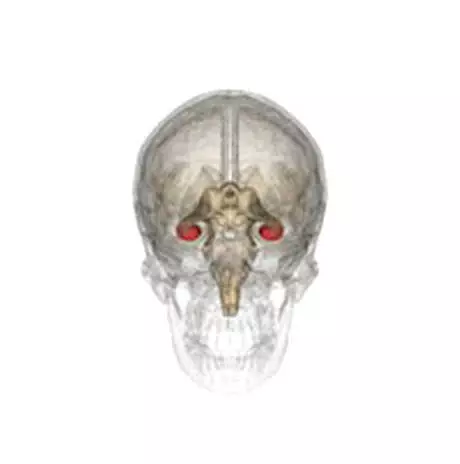

Öfkemiz, korkumuz, neşemiz… Aklınıza gelecek hemen hemen her duygusal durumunuzdan beyninizdeki limbik sistem sorumludur. Hipokampüs bu sistemin önemli parçlarından birisi olarak, beyninizin orta bölmesi olan temporal lobun içinde bulunur. İnsan dahil bütün memelilerde olduğu tespit edilmiştir.

Hipokampusların bütün memelilerde bulunduğunu söylemiştik. Primatlardaki hipokamp ile insanlardaki hipokamp birbirlerinin neredeyse tıpatıp aynıdırlar. Sadece insanların daha büyük hipokampusları vardır.

İnsan hipokampusu denizatına oldukça benzer bir yapıdadır:

Beynimizin sağ ve sol ana loblarına uzanan iki kuyruksu yapıdan oluşan hipokampus, insan beynine yandan bakıldığında bir denizatını andırır. Bu şekliyle uzun süre bilim dışı konularda bile tartışma yaratmıştır.